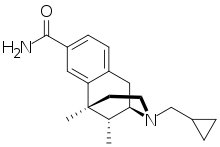

Morphinan derivatives

- Butorphanol—agonist/antagonist

- Nalbuphine—agonist/antagonist

- Levorphanol

- Levomethorphan

- Racemethorphan